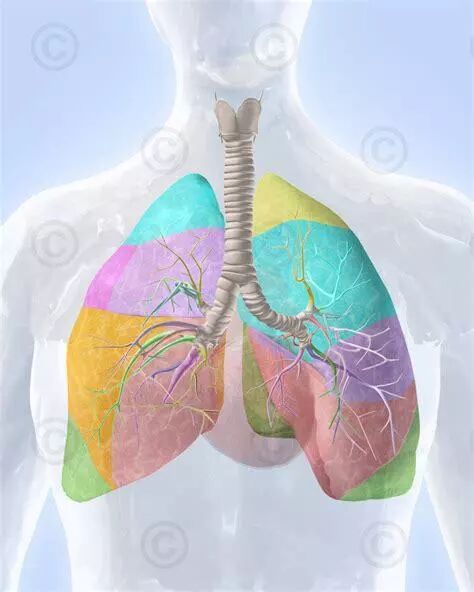

随着人们保健意识的增强,螺旋CT的普及, 越来越多的肺小结节得以早期发现。 对于病灶越小,尤其是位于肺深部的结节,肺部的多发结节, 常常难以定位并常需行肺段切除。 人体的左肺借斜形裂分成上、下两叶;右肺借横形裂和斜形裂分成上、中和下叶三叶。而左、右肺各有十个肺段, 由肺段支气管及其所属的肺组织组成。 肺段切除手术除了解剖操作困难,另一难点是不易准确标记出段与段的交界面,目前常规的白光胸腔镜使用膨胀萎陷法,需要等待20分钟, 就是由于上述问题的存在,导致手术时间的延长和手术难度的明显增加。 两种方法的区别详见下表: 为解决上述问题,最大限度使手术微创化, 2014年11月起在省内率先开展单孔胸腔镜手术的南京胸科医院杨如松团队, 又在最近引进了加拿大PINPOINT荧光胸腔镜,为肺段切除再添利器。 据杨如松院长介绍,荧光胸腔镜运用最新颖的技术:将荧光造影剂吲哚菁绿通过静脉或局部注射,与血红蛋白或白蛋白结合后,释放荧光,从而在手术中显像。 荧光胸腔镜与普通白光电视辅助胸腔镜不同的是: 术中对定位肺小结节区域进行荧光显影以及肺段平面的定位,病灶或肺段立刻“显露真身”,从而达到精确切除肺结节或肺段的目的,并最大程度地保留患者肺功能。 目标肺段“精准切除”此外,荧光造影剂吲哚菁绿没有放射性,不参与体内化学反应,无辐射,无毒副作用,且排泄快,病人非常安全。同时术中实时评估, 手术操作、观察同步进行,进而缩短了手术时间。 据杨院长介绍,运用加拿大PINPOINT荧光胸腔镜技术可以 最大限度减少正常肺组织的损伤,进而最大限度保留肺功能,结合我院在省内最新开展、业已多年、技术纯熟的单孔胸腔镜技术和非插管全身麻醉技术; 我科的肺段手术可以使患者创伤更小,恢复更快,从而让患者在极致微创的理念下,健康更多受益。